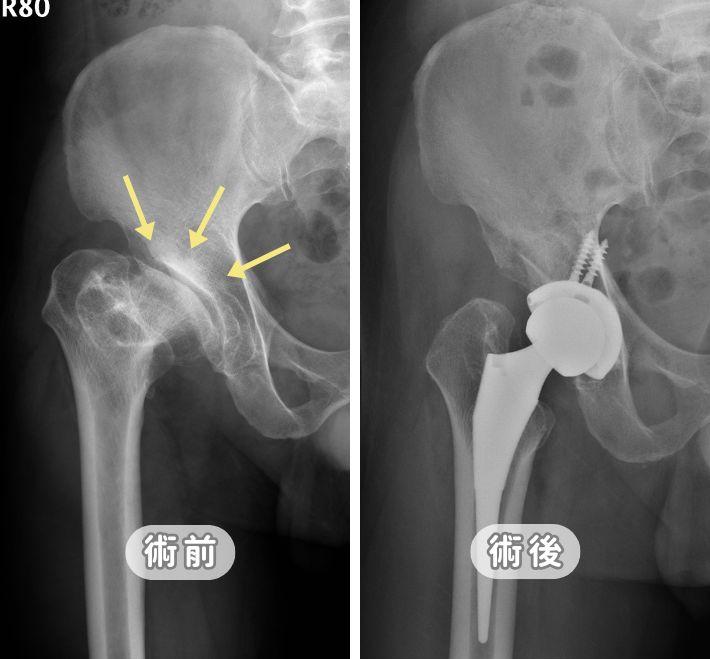

髖關節置換手術免復健:張建鈞醫師保留肌肉和天然關節囊

擔心髖關節手術後脫位與漫長復健?張建鈞醫師採用前外側微創入路,達成組織零切斷並完整「保留天然關節囊」。此技術能守住大腦本體覺,讓您術後不需刻意復健、行走自然、住院僅2-3天。適合追求快速康復與高穩定度的髖關節退化患者。

鼠蹊部隱隱作痛是「髖關節退化」嗎?30秒自我檢測與治療方法

鼠蹊部隱隱作痛、走路跛行?小心是髖關節退化警訊!本文由張建鈞醫師詳解腹股溝與鼠溪部內側痛成因。內附居家自我檢測方法與微創手術恢復期評估,了解更多。

微創人工髖關節手術全攻略:傷口小、免復健、重新大步走路

髖關節疼痛導致走路吃力、無法蹲下?張建鈞醫師解析「微創人工髖關節置換術」。詳解正位前開與創新前外側技術,如何做到不傷肌肉、術後當天即可下床。內含人工關節材質比較、自費費用建議與術後康復指南,助您精準評估,重拾行動自由。